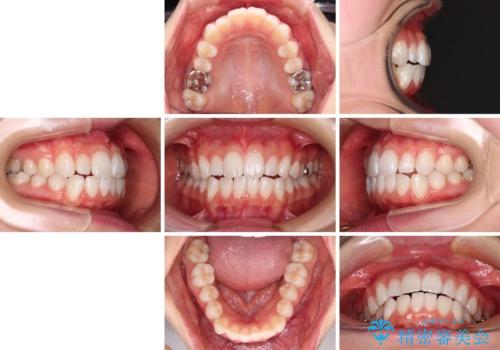

- 前歯の出っ歯と口元の閉じにくさを気にして来院された患者様です。

口元を積極的に引っ込めるために、上下左右の小臼歯4本を抜歯することとしました。